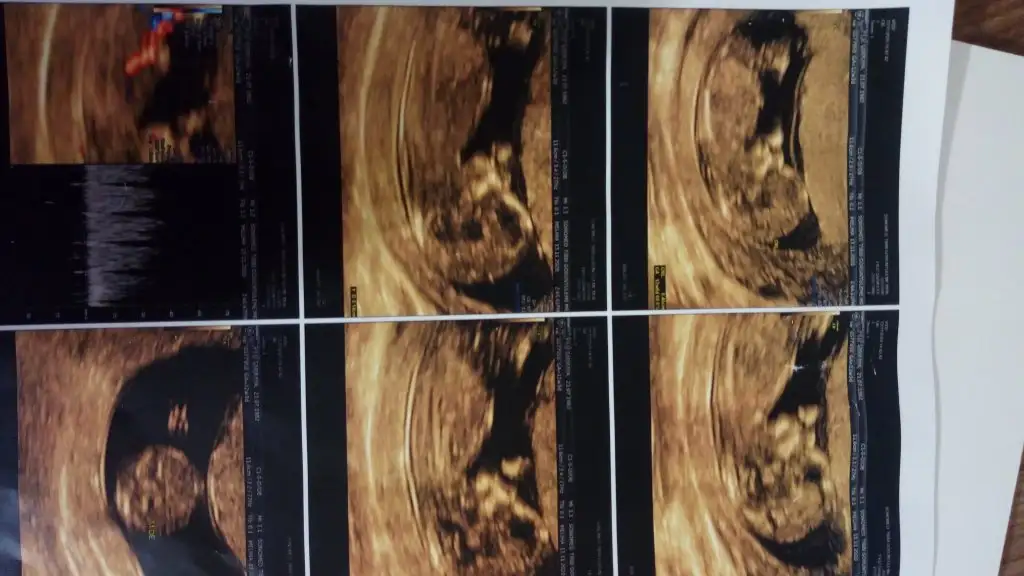

Tam net değil burda tam çıkmamış pipi kadar büyük gelmedi banaBaska boyle yok bide onden bacak arasi var

Yok tahmin edmedi dahaTam net değil burda tam çıkmamış pipi kadar büyük gelmedi banabaşka USG olursa 11 12 13 haftalar paylasirsin Dr tahmin ettimi

En iyi 11 12 13 haftalar olmalıMerhabagördüğüm kadarıyla tahmin yapıyorsunuz birde bana yorum yaparmısiniz. Eki Görüntüle 2720348

8+5 yazıyor uygun değil nub içinEki Görüntüle 2721344 10 haftalik usg yegenimin bi balar misiniz

Kız gibi sanki emin olamadım başka USG varsa paylaşınİkra meyra banada bakarmısınız12 haftalık resmi

Kız gibi sanki emin olamadım başka USG varsa paylaşınIkra meyra 13 hafta

Kız gibi sanki emin olamadım başka USG varsa paylaşın

Net degil